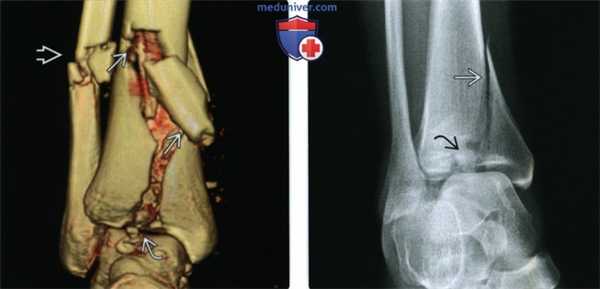

(Слева) При КТ на 3D-реконструкции определяется типичное расщепление нижней суставной поверхности большеберцовой кости при переломе ее дистального метаэпифиза. Кроме тою, выявляются косые переломы дистальных отделов диафизов большеберцовой и малоберцовой костей.

(Справа) Рентгенограмма голеностопного сустава в проекции суставной щели. Визуализируется вертикальная линия перелома, достигающая вдавленного центральною отдела нижней суставной поверхности. Однако при этом отсутствует типичный поперечный перелом большеберцовой или малоберцовой кости. В таком случае отличить перелом дистального метаэпифиза от изолированного перелома медиальной лодыжки можно по выраженности повреждения центральною отдела нижней суставной поверхности.